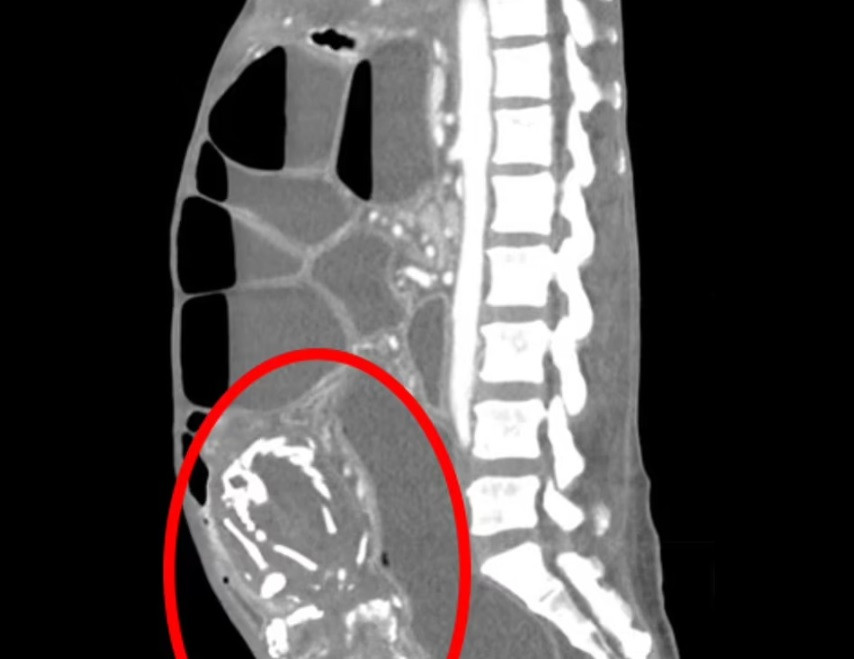

O femeie de 50 de ani din New York a murit din cauza malnutriției severe, după ce a purtat în pântec, timp de 9 ani, un făt nenăscut.

În urma investigațiilor, aceasta a descoperit că avea în pântec un făt nenăscut, pe care îl purta de nouă ani și care în timp se calcifiase.

Potrivit medicilor, fătul nenăscut i-a comprimat intestinele, fapt care a provocat blocaje, iar corpul femeii nu mai era capabil să absoarbă nutrienții vitali - ducând la înfometare.

Pacienta a refuzat tratamentul și a murit la 14 luni după sosirea în Statele Unite ale Americii.

Astfel de cazuri apar atunci când un făt care se dezvoltă în afara uterului moare în timpul sarcinii și nu este scos din organism. Moartea poate fi cauzată, în cele din urmă, de stop cardiac sau aritmie cardiacă, bătăi neregulate ale inimii, ca urmare a degradării țesuturilor.